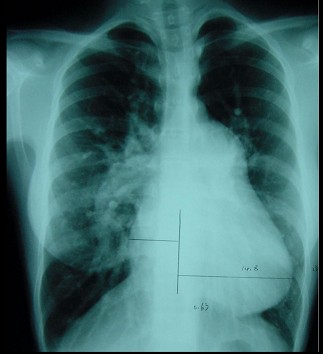

此心脏正位片描述正确的是 ( ) XXZ-1253.jpg

题型: 单选题 分类: 胸心外科学

• A.“中间型”心脏

• B.“二尖瓣型”心脏

• C.“主动脉瓣型”心脏

• D.“普大型”心脏

• E.“横位型”心脏